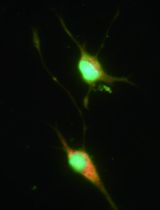

The basal forebrain is located close to the medial and ventral surfaces of the cerebral hemispheres that develop from the sub-pallium. It regulates multiple processes including attention, learning, memory and sleep. Dysfunction and degeneration of basal forebrain cholinergic neurons (BFCNs) are believed to be involved in many disorders of the brain such as Alzheimer’s disease (AD), schizophrenia, sleep disorders and drug abuse (Mobley et al., 1986). Primary cultures of BFCNs will provide an important tool for studying the mechanism of these diseases. This protocol provides a detailed description of experimental procedures in establishing in vitro primary culture of rat embryonic BFCNs.

The basal forebrain cholinergic system innervates the cerebral cortex and hippocampus. The normal function of the BFCNs is essential for normal sleeping, learning and memory. And the atrophy of BFCNs is considered as the early event of Alzheimer’s disease. Thus, the primary BFCNs culture will be the ideal cell model for AD research. In previous studies, primary BFCNs cultures were rarely used. Here, we present a reliable method to isolate and culture BFCNs from the embryonic rat septum which is simple, less time consuming than the previous method (Schnitzler et al., 2008). Our method will greatly facilitate studies of many critical aspects of BFCN function and cell biology.